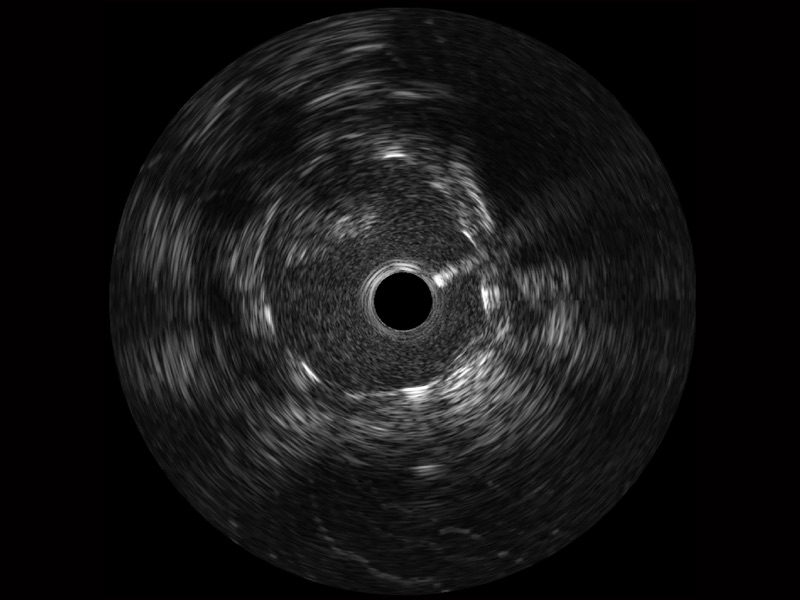

開(kāi)立寬頻IVUS圖像

傳統(tǒng)IVUS圖像

對(duì)比傳統(tǒng)IVUS導(dǎo)管成像,開(kāi)立寬頻IVUS圖像的近場(chǎng)支架梁顯影更細(xì)膩,遠(yuǎn)場(chǎng)中膜外血管仍清晰可辨,兼顧遠(yuǎn)中近,兼顧分辨力與穿透深度